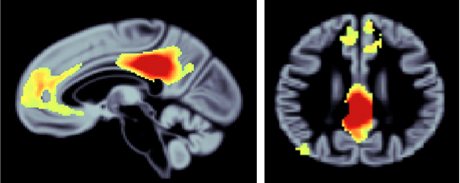

The researchers found that brain volume in the default network (a set of brain regions associated with internally generated thoughts such as memory) declined in both healthy and pathological aging. The researchers noted the greatest decline in Alzheimer’s patients and in those who progressed from mild cognitive impairment to Alzheimer’s disease. Reduced brain volumes in these regions were associated with declines in cognitive ability, the presence of known biological markers of Alzheimer’s disease and with carrying the APOE4 variant of APOE gene, a known risk factor for Alzheimer’s.

“While elements of the default network have previously been implicated in aging and neurodegenerative disease, few studies have examined broad network changes over the full adult life course with such large participant samples and including both behavioral and genetic data,” said Spreng. “Our findings provide evidence for a network-based model of neurodegenerative disease, in which progressive brain changes spread through networks of connected brain regions.”